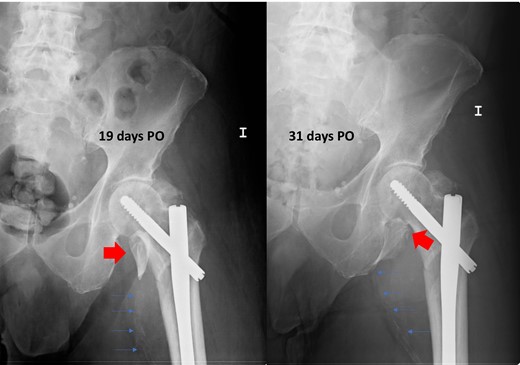

We present a case of an 80-year-old institutionalized man, who suffered an unstable intertrochanteric fracture of the left hip, type 31.A2.1 (AO-OTA) due to a low energy accident after falling from his own height. The patient previous medical history included bipolar disorder, hypertension, DM, and right inguinal herniorrhaphy surgery. The patient underwent closed reduction and internal fixation with an intramedullary nail type Gamma3 (Stryker Trauma GmbH Prof. Küntscher-Str. 1-5 24 232 Schönkirchen, Germany) of the fracture during the first 24 hours after injury. The surgical procedure was performed without any intraoperative complications. He was discharged from the hospital on the sixth postoperative day, asymptomatic, with a postoperative hematoma in the left thigh, walking with a walking frame, with a postoperative radiographic control showing a correct nail placement without alterations and with an hemoglobin value (HGB) of 10.7 g/dl and a hematocrit value (HCT) of 30.8%. On the 18th postoperative day, he suffered a fall after having a syncopal episode, so he went to the emergency room and was admitted to the hospital for study. The hematoma in his thigh was evolving correctly, and the radiographs remained unchanged with respect to the previous ones. He was discharged two days later. One month after surgery, he returned to the hospital due to persistent pain, volume increase and progressive hematoma in the left thigh. The blood analysis showed an anemia (HGB 9.5 g/dL, HCT 29%). The pedia pulse was present and the posterior tibial pulse was weaker than the contralateral but also present. An X-ray showed a superior and medial displacement of the lesser trochanter compared to previous radiographs and a medialization of the femoral artery, visible because it was calcified (Fig. 1). A Doppler ultrasound was performed showing a hypoechoic lesion with turbulent flow inside compatible with pseudoaneurysm at the level of the deep femoral artery or one of its branches. The study was completed with a CT angiography that confirmed the presence of a pseudoaneurysm of 7.3 × 6.7 × 6 cm at the level of the deep femoral artery at the beginning of the lateral circumflex branch (Fig. 2). At that time, the patient was referred to the Interventional Radiology Service. The vascular lesion was immediately treated by femoral transcatheter embolization with two distal coils in the lateral circumflex artery measuring 3 and 4 mm (Axium 3D Medtronic 9775 Toledo Way Irvine, CA 92 618 USA) and proximal embolization by a liquid embolic agent, Onyx 34 (Covidien 106-108 Rue la Boetie 75 008 Paris, France).

Postoperative radiographs after intertrochanteric fracture synthesis with trochanteric nail 19 and 31 days after surgery. Secondary displacement of LT can be observed (wide arrows) and of the calcified femoral vessels (thin arrows), indirect signs of the presence of a pseudoaneurysm.